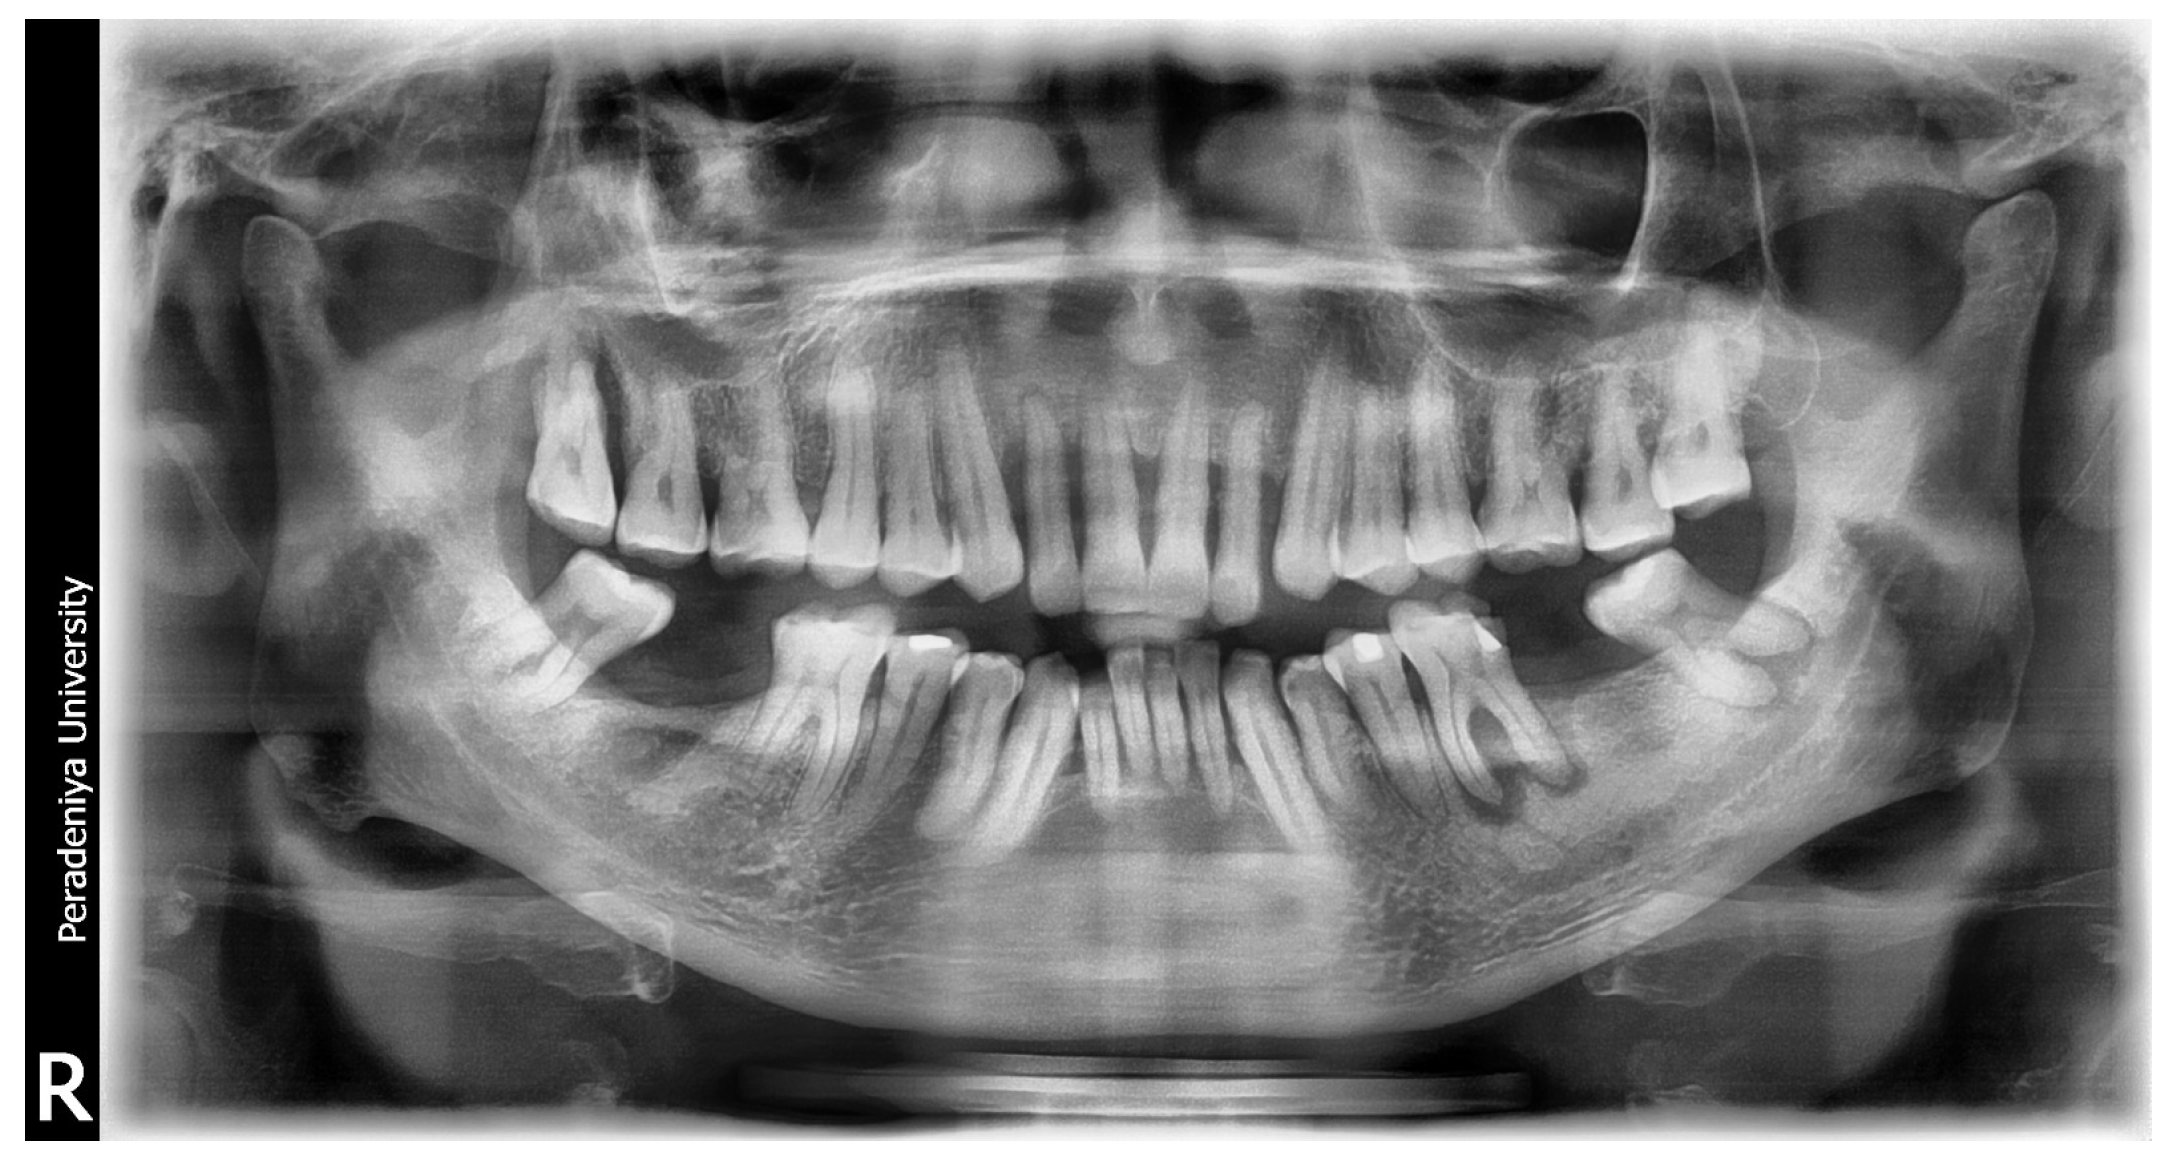

Figure A5.

Sample DPT image 02.

Figure A6.

AI-generated report for DPT image 02. This report received a low subjective score for identifying oral conditions in DPT image 02.